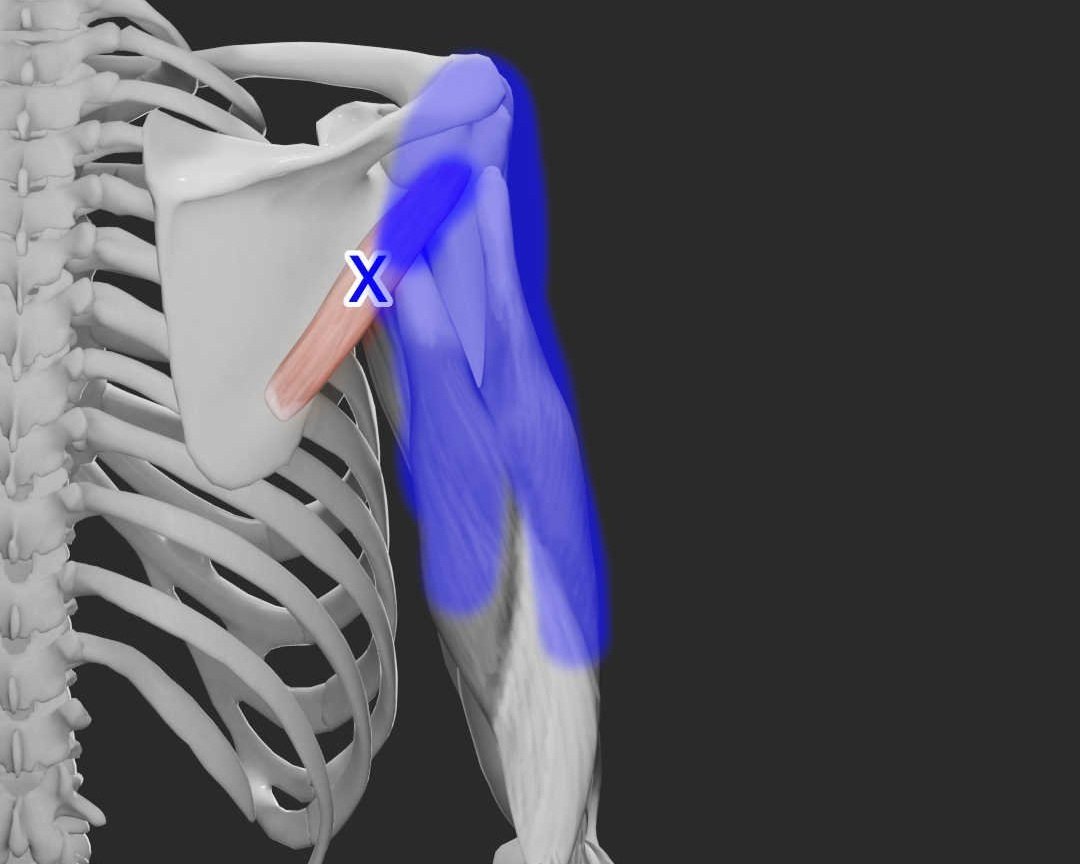

Acupuncture for Subscapularis Pain

As one of the rotator cuff muscles, subscapularis trigger points can cause back of arm, back of shoulder, and wrist pain. Learn more about subscapularis pain and how acupuncture and dry needling can help.